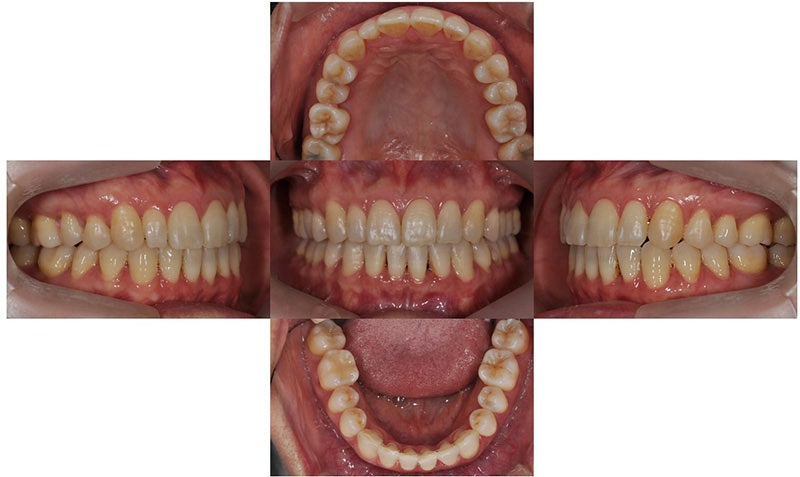

다음으로는 중년에 치아교정을 진행하신 분들의 치아교정 전후 및 후기입니다.

2019.12

위 환자는 만 49세 여자 환자로 아래 치아가 갈수록 더 틀어진다는 주소로 치과에 내원하셨습니다. 아래 치열이 점점 틀어져 잇몸 관리가 쉽지 않다고 하셨습니다. 안모의 돌출은 없어 비발치로 교정치료를 진행하기로 하였습니다.

2021.2

약 2년 간의 비발치 교정치료 동안 큰 잇몸퇴축이나 black triangle 등의 부작용 없이 교정 치료가 마무리되었습니다. 교정 치료 전후 미소 사진을 비교해보면 교정 치료 이후에 좀더 자신감있게 활짝 웃는 모습을 확인할 수 있었습니다.